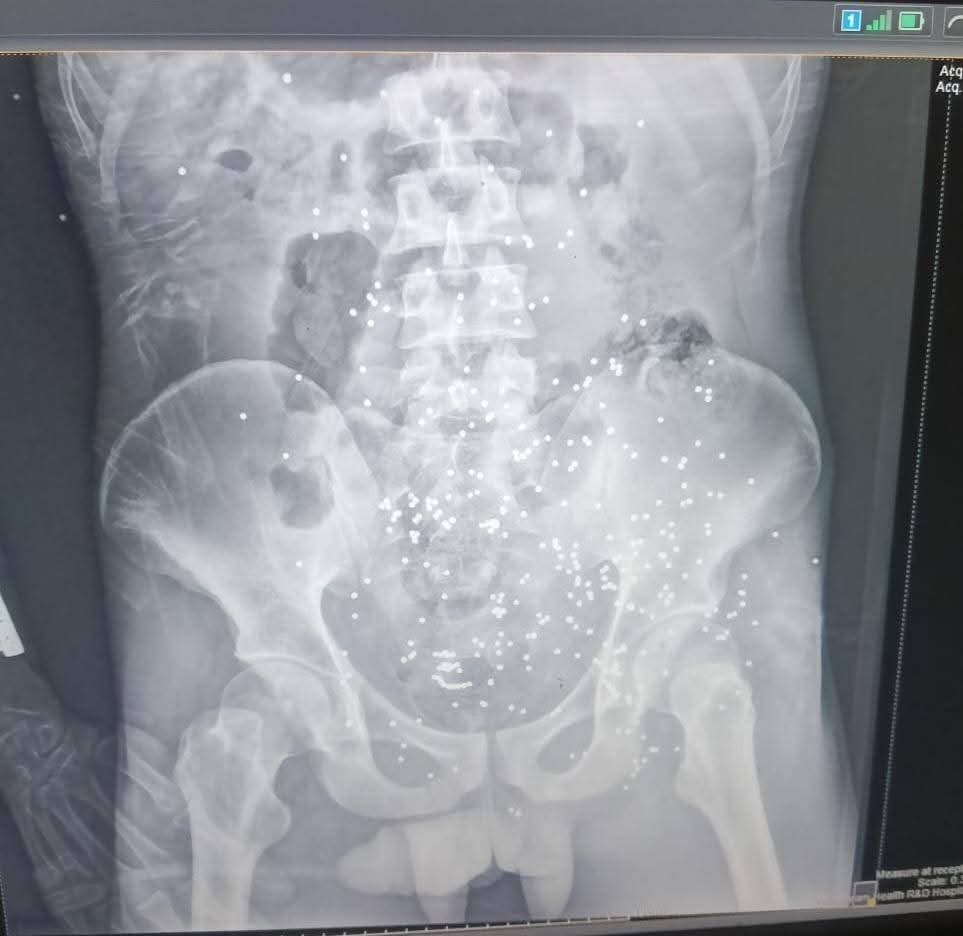

أعلنت الدكتورة نادية مكرم وكيلة وزارة الصحة بالمنيا بانه في الساعات الأولى من عيد الاضحي المبارك حضر إلى طوارىء مستشفي ملوي التخصصي شاب في العقد الثالث من العمر فى حالة سيئة نتيجه حادث طلق ناري خرطوش بالبطن.

مما أدى إلى إصابات متعدده بالبطن واشتباه اصابه بالوريد المغذى للطرف السفلى واشتباه اصابه فى المثانه ونزيف شديد من أماكن دخول الخرطوش، وتم دخول المريض إلى العمليات مباشره ،وتم عمل استكشاف بالبطن حيث تبين وجود نزيف داخلى بالبطن وإصابات بالامعاء ومساريقا البطن ومنديل البطن.